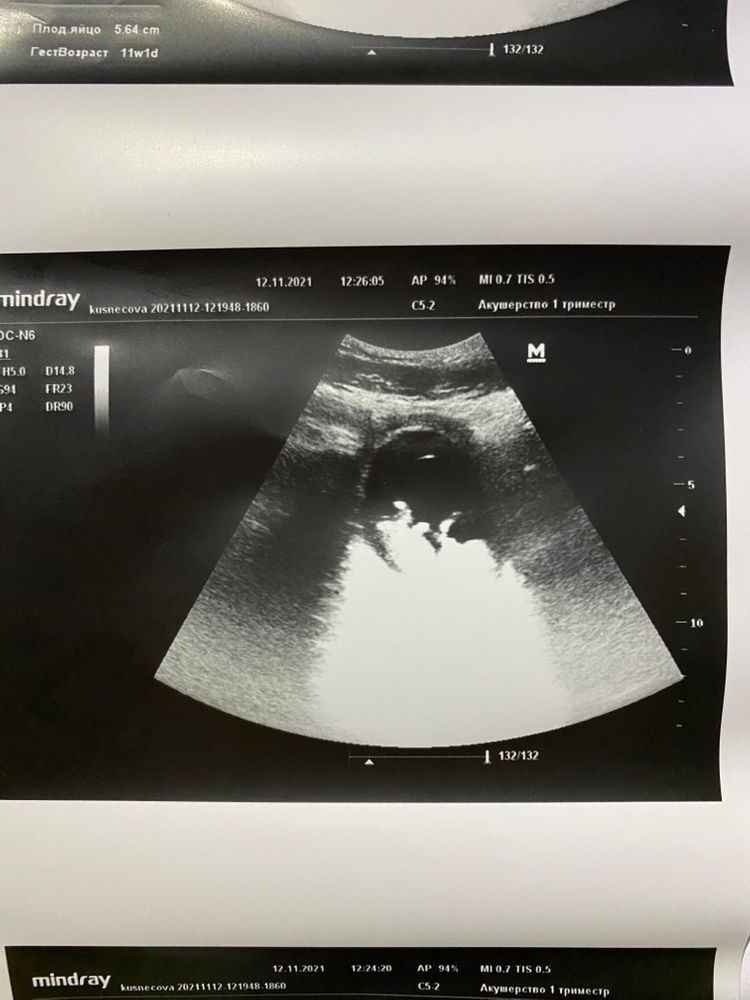

Девочки , всем привет ! Была на узи , срок 11 и 1 день, предположили мальчика . Есть тут экспорты ?)

Девочки , всем привет ! Была на узи , срок 11 и 1 день, предположили мальчика . Есть тут экспорты ?)

Юлия Sonnце, у меня срок здесь как я и написала . То , что написано на экране не совпадает с реальным сроком . В предыдущем посте 12 недель.

Анастасия Кузнецова, в любом случае, не видно кто на ваших фото.

Мне в 11,6 верно сказали, но у вас 11,1, совсем как то мало, скрининг по моему с 11,3 минимум делают..если хотите, сдайте кровь на пол плода, расскажет раньше и точнее любого узи

У Вас же срок больше. Какие 11 недель? А в предыдущем Вашем посте 14 вообще написано.